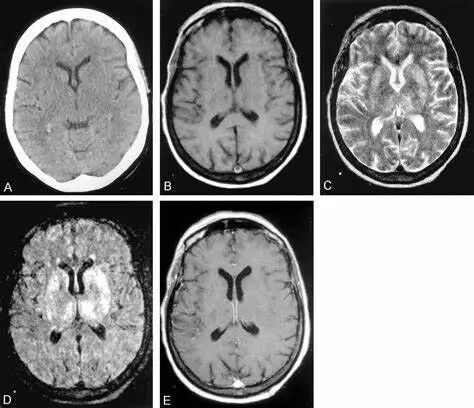

西尼罗病毒神经系统侵袭性病变可表现为脑炎、脑膜炎或急性非对称性弛缓性麻痹。伴有肌无力和弛缓性麻痹的脑炎高度提示西尼罗病毒感染。其他神经系统表现包括:震颤、肌阵挛及帕金森特征(如,强直、姿势不稳和运动徐缓)。

脑实质受累提示脑炎